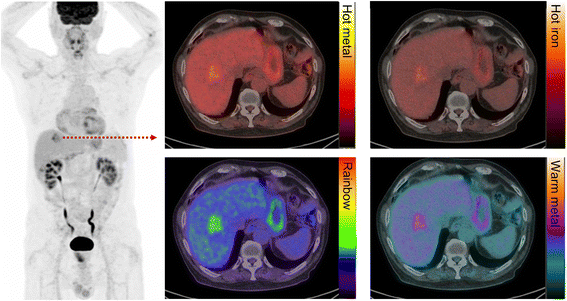

Our preference is to have the most intense voxels in the normal liver appearing just below the middle of the grey scale range, which will be a light to mid-grey (Fig. 1a). Use of a colour scale is required for superimposition of functional images over the CT. We prefer to use the "rainblow" colour scale that has low activity regions displayed in the blue-green range and higher intensity regions in the orange-red spectrum. With this colour scale, the liver will generally appear blue with flecks of green with adjusgment if not (Fig. 1). This corresponds to an upper SUV window threshold of 8–10 and will usually achieve an appropriate contrast, except in very large patients in whom this may make the liver too dark. This is because adipose tissue contributes to the weight correction of administered activity, which is used for SUV calculation, but does not itself take up FDG. This means that more FDG is available for uptake in other tissues, including the liver. However, this may be counteracted by deposition of fat in the liver in obese subjects. This will usually be apparent by virtue of increased relative uptake in the spleen, which is generally marginally less intense than the liver. The brain will usually be nearly black with this scaling. This is unless cortical glycolytic activity is reduced by metabolic processes, especially by hyperglycaemia, or neurological conditions such as dementia. In children requiring general anaesthesia during the uptake and scanning procedure, cortical activity can also be significantly reduced. There are also changes in the brain during childhood maturation [2].

The PET window intensity is adjusted so that the liver appears light to mid-grey on the grey scale, corresponding to flecks of green in the liver on the rainbow colour scale. Despite the difference in SUVmax of the liver secondary to differences in weights of the two patients (a and b), the liver intensity this appears the same in both patients

Patient with metastatic colorectal carcinoma and hepatic metastasis. The fused image is presented in different colour scales. We recommend using the “rainbow” scale owing to the superior tumour-to-liver contrast compared to other commonly used colour maps

We dislike colour scales with a continuous spectrum of a single colour, such as the commonly used “hot metal” scale, as these provide poor contrast between low and high intensity, and background CT images. The human eye is very sensitive in detecting differences of intensity within a grey scale but not so good within a single colour spectrum. Consequently, with “hot metal” or similar colour scales, it is difficult to qualitatively assess an image and know where the intensity of abnormality lies within in the spectrum. Moreover, the highest intensity on this scale is sometimes white, which is essentially uninterpretable when superimposed on a grey scale CT image.